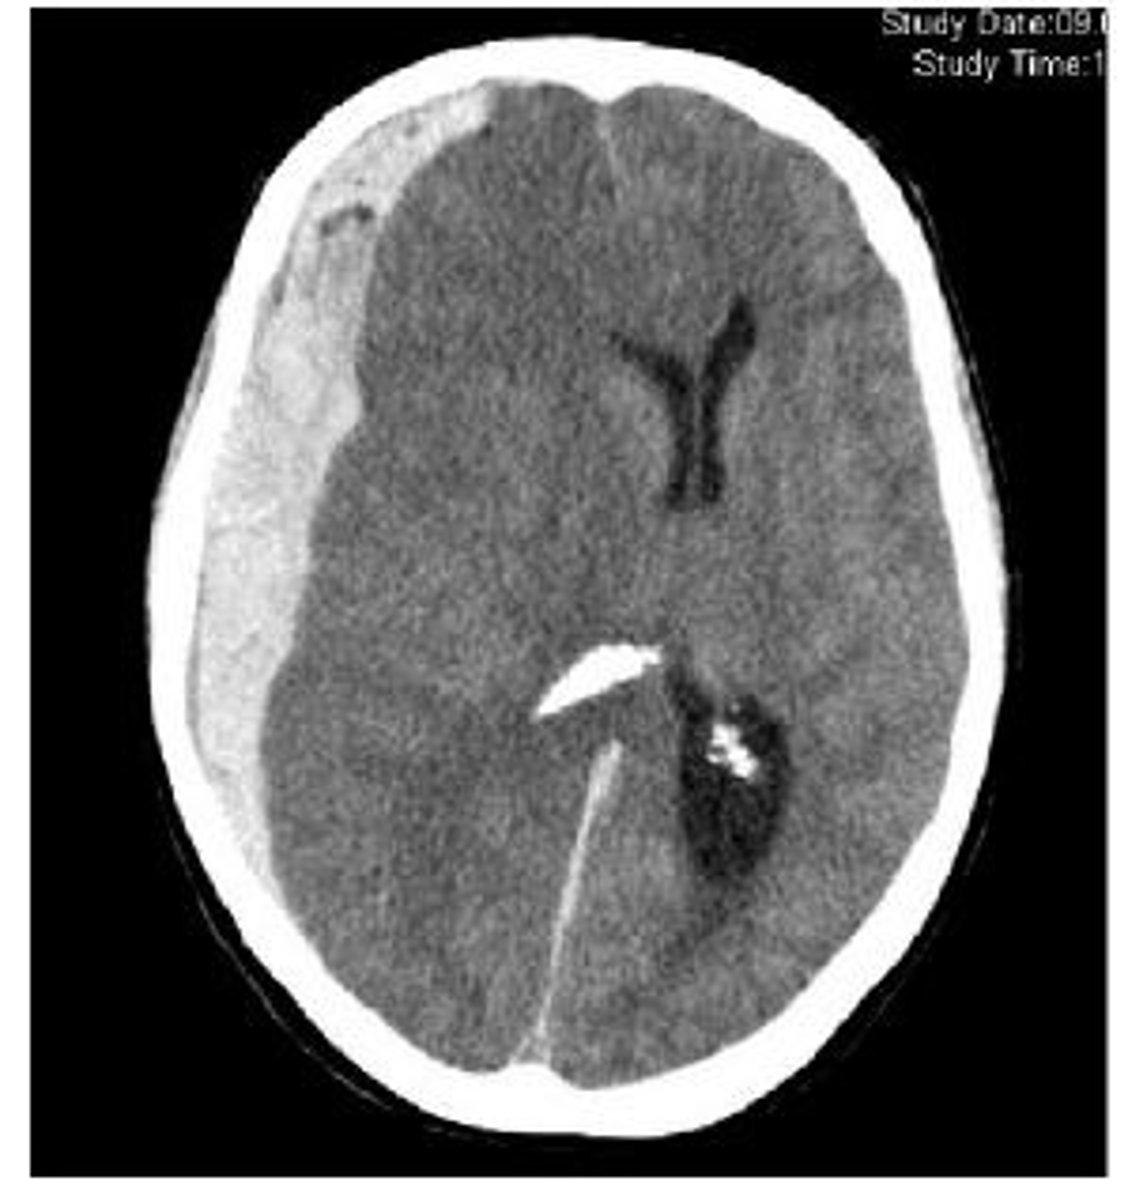

Subarachnoid hemorrhage

bleeding between arachnoid mater and pia mater where the blood replaces the CSF and on CT it shows blood tracing down into sulci

Subarachnoid hemorrhage causes

trauma, rupture of intracranial aneurysm with a severe headache of rapid onset